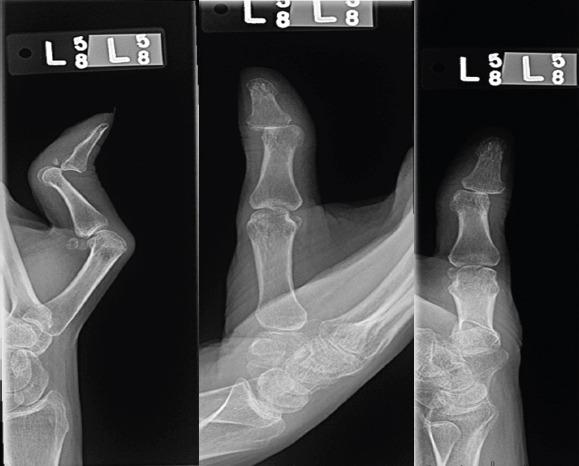

Thumb boutonniere deformity, commonly associated with autoimmune arthropathies, presents as metacarpophalangeal (MCP) joint flexion and interphalangeal (IP) joint hyperextension. Literature guiding management remains incomplete and out-of-date, and it largely addresses low-demand populations. IP joint dislocation is a particularly severe presentation that notably has only been reported once before.

拇指纽扣畸形通常与自身免疫性关节病相关,表现为掌指(MCP)关节屈曲和指间(IP)关节过伸。指导治疗的文献仍然不完整且过时,并且主要针对需求较低的人群。IP关节脱位是一种特别严重的表现,此前仅被报道过一次。

我们报告了一例罕见的1型拇指纽扣畸形伴IP关节脱位的病例,患者为一名42岁、需求较高且有自身免疫性疾病病史的女性。我们描述了使用MCP关节融合术和临时IP关节穿针固定成功治疗这种严重拇指畸形的过程,该治疗方法保留了拇指的功能和稳定性。在1年的随访中,患者报告拇指功能良好,未出现IP关节脱位的情况。